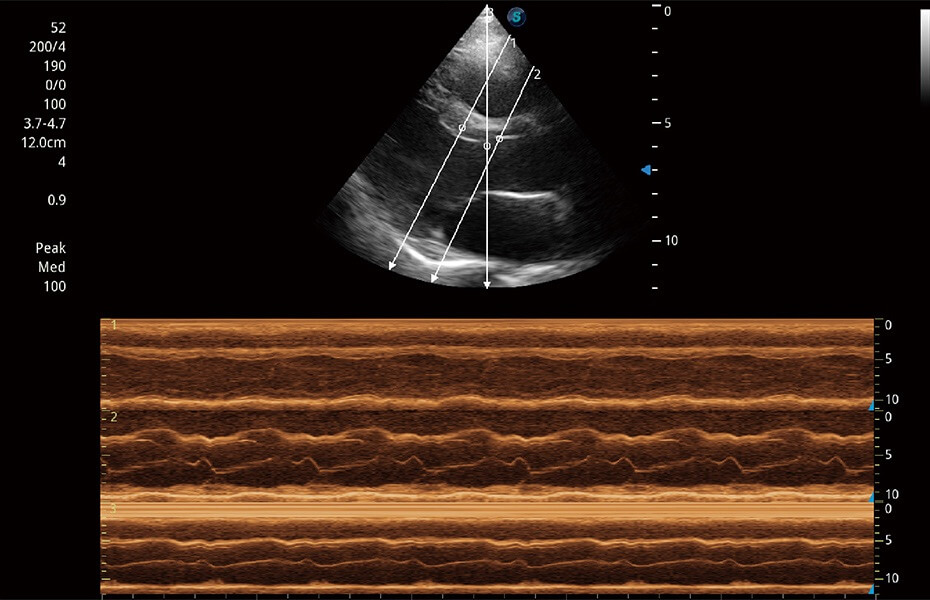

ProPet 60 作為一款高端臺(tái)式動(dòng)物超聲設(shè)備,為動(dòng)物醫(yī)生的日常診斷提供了一系列貼合動(dòng)物臨床需求、解決臨床實(shí)際問(wèn)題的高級(jí)成像功能。憑借全系列高清探頭,滿(mǎn)足醫(yī)生對(duì)腹部、心臟、生殖、淺表、肌骨等成像的所有需求,切實(shí)幫助您提升檢查效率,提高診斷信心。